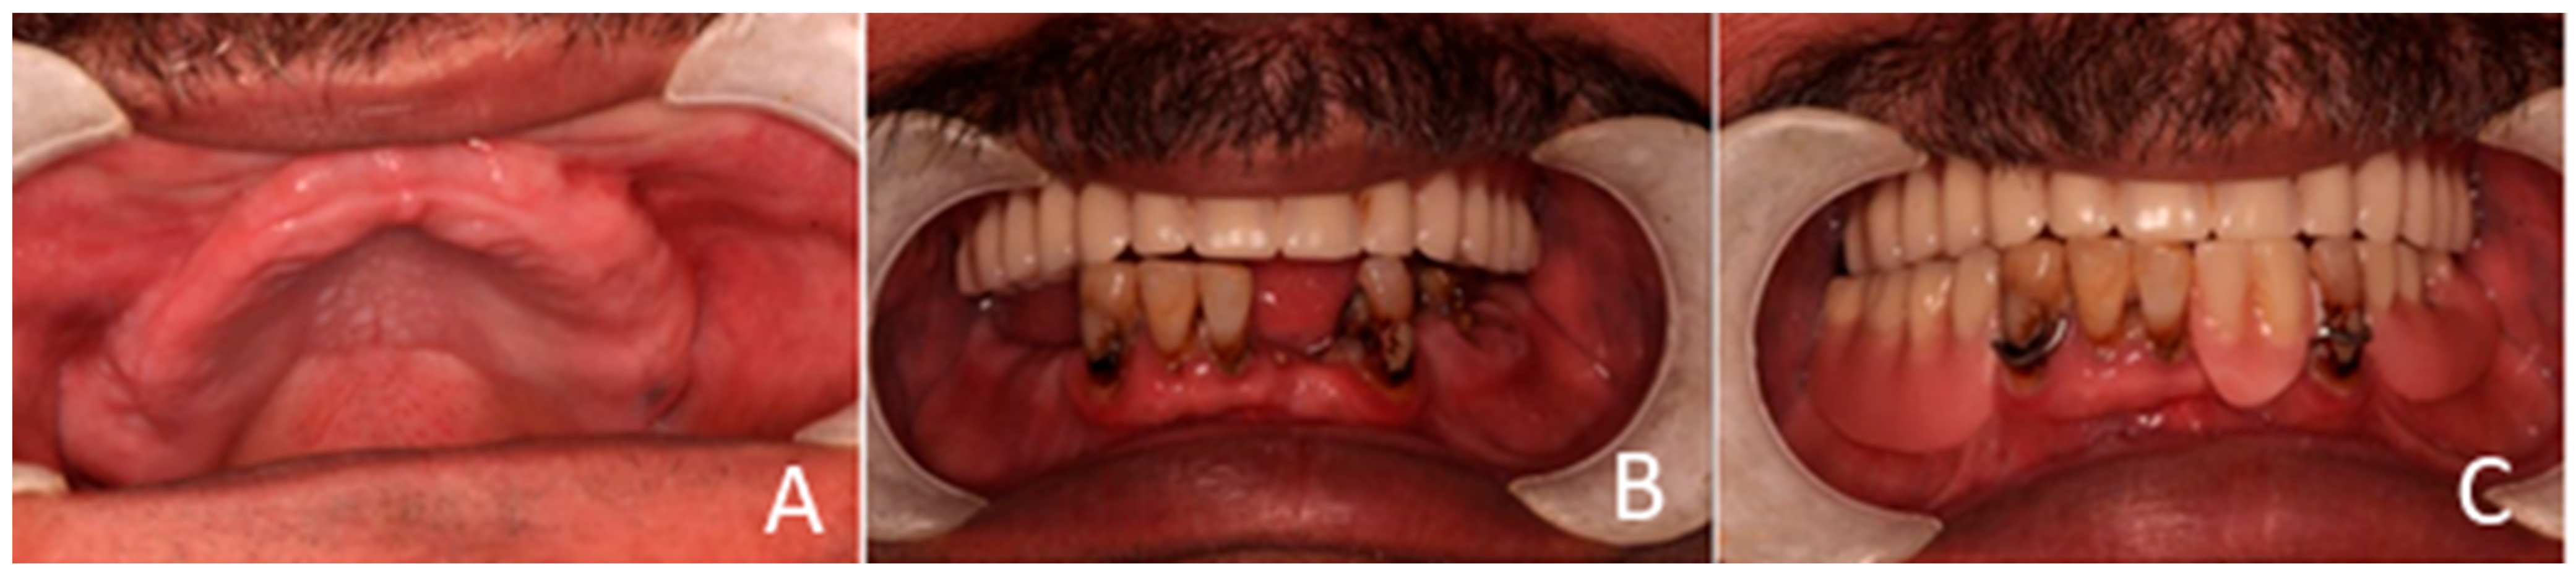

Each telescopic crown was sandblasted on the internal surfaces, then placed in an ultrasonic bath and treated with the manufacturer-specified “Bredent” solution. A resin cement was utilized to bond each telescopic crown to its respective zirconia abutment. The arches were scanned once again and sent to the lab for the fabrication of segmented zirconia bridges, which were subsequently provisionalized with PEEK crowns (Figure 11, Figure 12 and Figure 13).

Figure 12. PEEK telescopic crowns are shown covering the implants’ abutments.

Figure 14. The final prostheses.